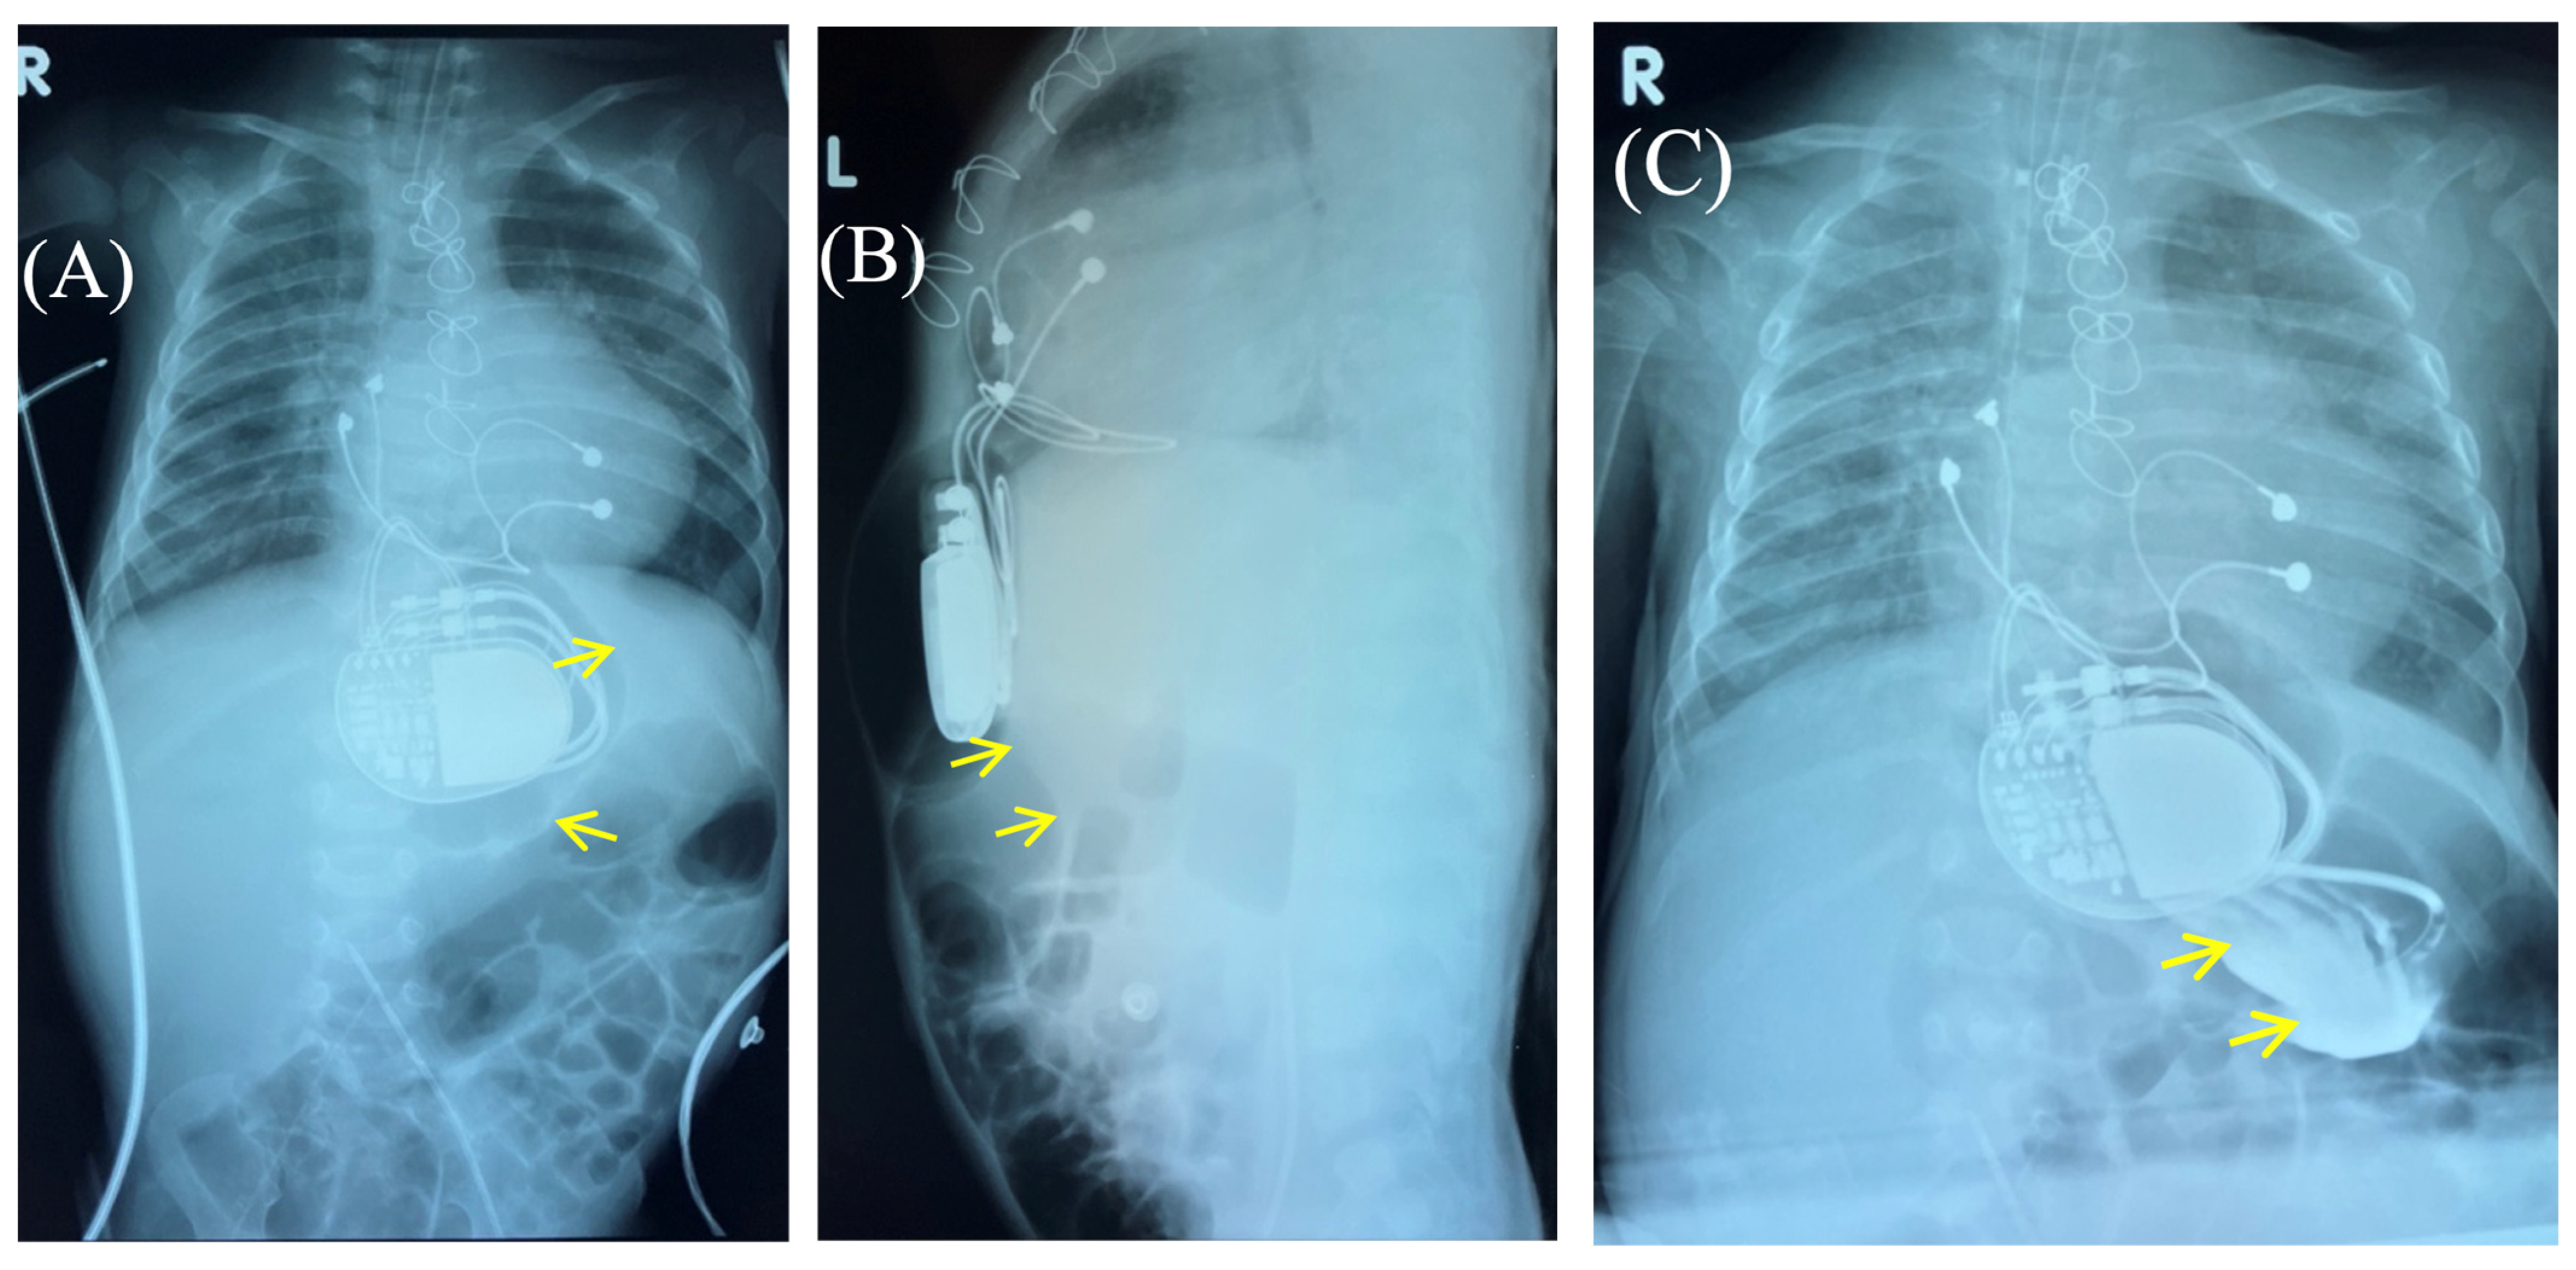

Figure 2.

Chest X-ray—frontal (A) and lateral (B) view. Chest X-ray shows no pneumothorax, but pneumopericardium, pneumomediastinum and air in the pacemaker pocket site (red arrow) are present. One can also see the pacemaker electrodes (yellow arrow), the pulse generator (black asterisk), and the wire ligature (pink arrow). R: right side.

Figure 3.

Control of the passage of radiocontrast agent (yellow arrow) through the gastrointestinal tract to exclude perforation of a hollow organ of the abdominal cavity. Frontal (A,C) and lateral (B) view of the chest X-ray 1 h (A,B) and 2.5 h (C) after radiocontrast agent administration. R: right side; L: left side.

Fluoroscopy and chest and abdominal radiography revealed no signs of pneumothorax. A demarcated area of free air was visualized in the upper anterior abdominal wall along the midline, projecting to the pacemaker pocket. The passage of radiocontrast agent through the gastrointestinal tract was observed dynamically and found to be normal. No signs of hollow organ perforation or intestinal obstruction were detected (Figure 2, Figure 3 and Figure 4).

Figure 4.

Chest X-ray examination—frontal (A) and lateral (B) view. Chest X-ray shows no pneumothorax, but pneumopericardium, pneumomediastinum with air are present at the pacemaker pocket site (red arrow). Radiocontrast agent (yellow arrow) at the gastrointestinal tract.

Figure 6.

Chest X-ray after surgery debridement and closure of the wound. Chest X-ray (frontal (A) and lateral (B) view) shows no signs of pneumothorax, pneumopericardium, pneumomediastinum with minimal air at the pacemaker pocket site. (C) The healed sternotomy and the projection of the pacemaker pocket 12 days after revision and sanitation.